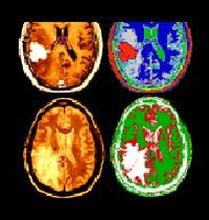

Primary tumours of the central nervous system (CNS tumours) originate in the brain or the spinal cord. With about 510 newly diagnosed paediatric patients in Germany per year, CNS tumours are the most common solid tumours. Following leukaemias, they account for the second most frequent childhood cancer (with about 24%). There are many types of primary brain tumours, such as low-grade or high-grade gliomas, medulloblastomas, embryonal, non-rhabdoid CNS tumours (before known as CNS-PNET), pineoblastomas, ependymomas, and choroid plexus tumours. Here, you will find information on primary brain tumours. Other pages will offer information on CNS metastases of other cancers.